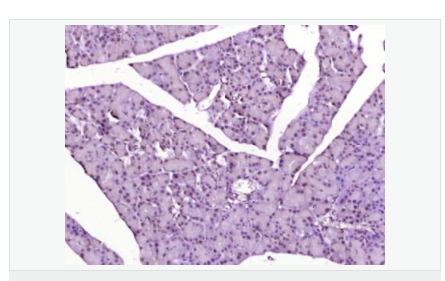

| 產品應用 | WB=1:500-2000 ELISA=1:5000-10000 IHC-P=1:100-500 IHC-F=1:100-500 IF=1:100-500 (石蠟切片需做抗原修復) not yet tested in other applications. optimal dilutions/concentrations should be determined by the end user. |

| 產品介紹 | Acts as a growth inhibitor. Can activate TP53/p53, causes G1 arrest and collaborates with CDKN2A to restrict proliferation, but does not require either protein to inhibit DNA synthesis. Redistributes CDKN2A into the nucleoplasm. Involved in maintaining chromosomal stability. There are two isoforms. Function: Acts as a growth inhibitor. Can activate p53/TP53, causes G1 arrest and collaborates with CDKN2A to restrict proliferation, but does not require either protein to inhibit DNA synthesis. Redistributes CDKN2A into the nucleoplasm. Involved in maintaining chromosomal stability. Subunit: Interacts with CDKN2A and MDM2. Subcellular Location: Nucleus. Tissue Specificity: Widely expressed at low levels in most tissues, with highest levels in pancreas, lung and liver. Expression is decreased in primary tumors including lung, liver, breast, pancreas and kidney carcinomas, chronic lymphocytic leukemia and diffuse large B-cell lymphoma. Post-translational modifications: Ubiquitinated; mediated by MDM2 and leading to its subsequent proteasomal degradation. Similarity: Belongs to the TBRG1 family. Contains 1 FYR C-terminal domain. Contains 1 FYR N-terminal domain. SWISS: Q3YBR2 Gene ID: 84897 Database links: Entrez Gene: 84897 Human Entrez Gene: 21376 Mouse Omim: 610614 Human SwissProt: Q3YBR2 Human SwissProt: Q3UB74 Mouse Unigene: 436410 Human Unigene: 28689 Mouse Unigene: 129282 Rat Important Note: This product as supplied is intended for research use only, not for use in human, therapeutic or diagnostic applications. |